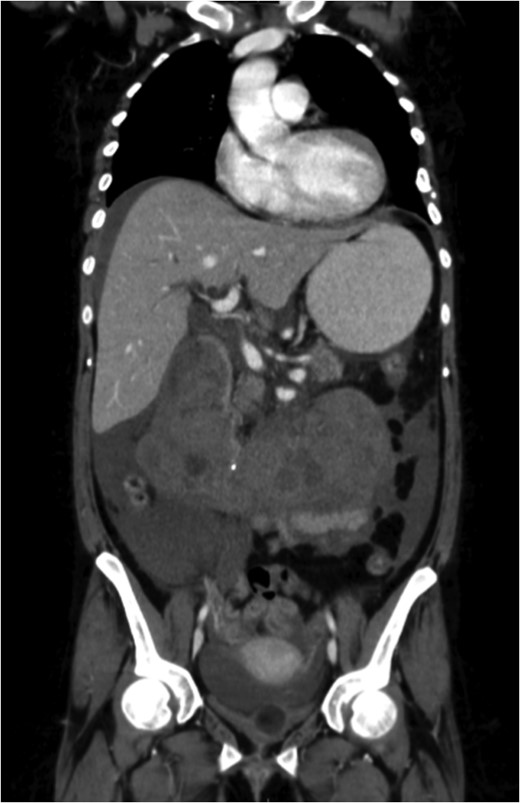

Excessive tilting of the IVC filter causes the hook of the filter to appear outside of the lumen of the IVC.

The patient's coagulopathy was treated and she underwent a laparotomy and evacuation of a large duodenal haematoma. After division of adhesions, a tense duodenal wall was revealed with splitting of the serosal layer. A large haematoma, of about 500 mls volume, was removed from the subserosal layer without breach of the muscularis. The penetrating strut of the IVC filter was able to be palpated within the duodenal wall but was not on view after haematoma removal. There was considerable inflammation of the retroperitoneum as well as scarring from the previous arterial bypass surgery. There was no contamination of the peritoneum with bowel contents. It was thought preferable to remove the IVC filter via the transvenous route rather than expose the IVC and risk large blood loss and arterial graft contamination in the event of duodenotomy.